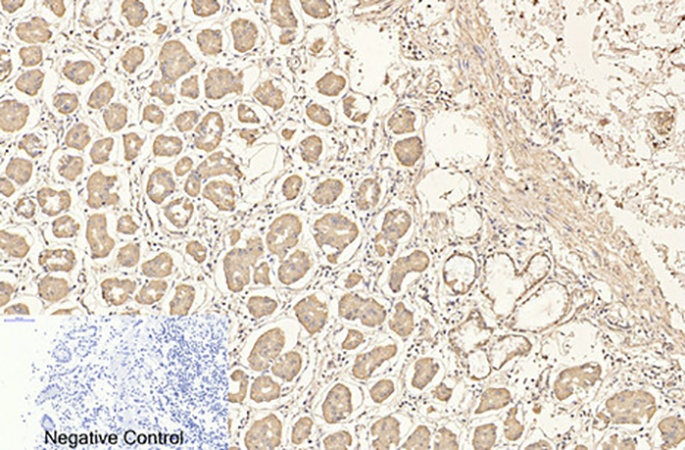

What makes ABM40070 stand out isn’t just specs—it’s adaptability. We’ve seen it shine in flow cytometry (1:100 dilution, FITC/PE conjugates available), Western blotting (1:500, crisp 55 kDa bands), and even immunohistochemistry on FFPE tonsil sections (1:200, highlighting germinal center T cells). A recent study on rheumatoid arthritis used it to track CD4+ T cell infiltration in synovial fluid, correlating CD4 density with TNF-α levels—something their old antibody couldn’t resolve. Pro tip: Pair it with Abbkine’s CD25 antibody (ABM40120) for regulatory T cell phenotyping; users report a 40% boost in gating accuracy. For high-specificity CD4 monoclonal antibody for flow cytometry, this combo is a game-changer for labs sorting rare T cell subsets.